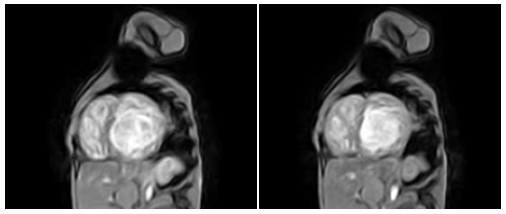

80 years old patient with no known cardiovascular risk factors had been symptomatic for dyspnea from long time ago and physical examination evidenced cardiomegaly. The electrocardiogram showed incomplete left bundle branch block. Echocardiography demonstrates trabeculations, ventricular enlargement and prominent myocardial walls recesses (Figure 1). In this case LVNC has had a good clinical outcome, due patient’s age. Bad news for adult patients with heart failure and LVNC is that when this association is diagnosed can only have two evolutions, to stabilize or get worse. When left ventricular dilation and functional impairment are present, the annual death rate is about 35%, same mortality as idiopathic dilated cardiomyopathy.17 Definitely, prognostic factors are not different from dilated cardiomyopathy. Ejection fraction deterioration and symptoms as major predictors of poor outcome. Comments: LVNC observed in advanced stages of life, associated to ventricular dilation and impaired systolic function has the same prognosis than idiopathic dilated cardiomyopathy (DCM).

Figure 1 CMR with Fast Field Echo sequence. Left image: the heart in diastole, shows left ventricular hypertrabeculation. Right image: In systole (with systolic dysfunction) absence of contraction in the trabecular region is observed. The ventricular contractile function is maintained from the basal segments.